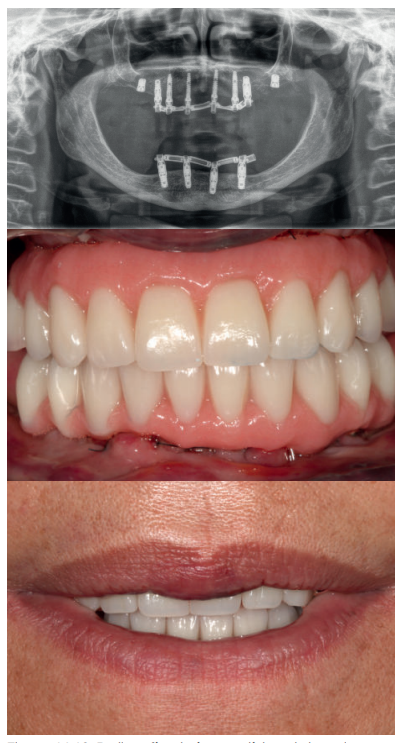

Una vez finalizada la confección de la prótesis, se coloca en el paciente. En las imágenes podemos observar el resultado clínico final y la radiografía, donde puede verse el ajuste de las estructuras sobre los implantes (Figuras 24-26).

Podemos observar la comparación entre el estado inicial y el resultado final, que satisface los deseos estéticos y funcionales de la paciente y además recupera la dimensión vertical perdida con las prótesis removibles (Figuras 27-30).